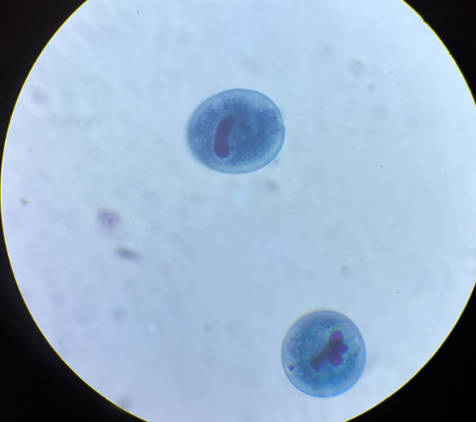

cyclospora cayetanensis oocysty

cyclospora cayetanensis oocysty